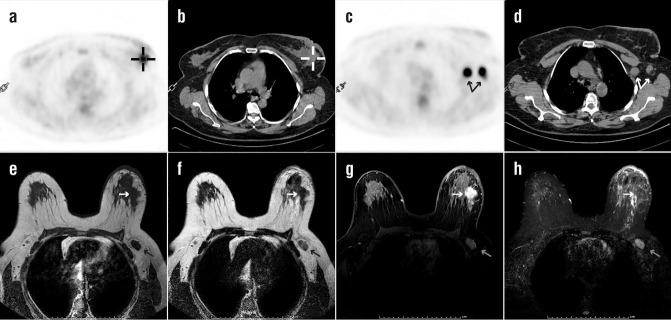

Breast carcinoma is the most common type of cancer in females. This study aims to compare fluorine-18-fluorodeoxyglucose (F-FDG) uptake pattern and apparent diffusion coefficient (ADC) value for the detection of the primary tumour and axillary metastases of invasive ductal breast carcinoma.

This study included 40 breast carcinoma lesions taken from 39 patients. After staging by positron emission tomography-computed tomography (PET/CT) and diffusion-weighted magnetic resonance imaging (MRI), breast surgery with axillary lymph node dissection or sentinel lymph node biopsy was performed.

Primary lesion detection rate for PET/CT and diffusion-weighted MRI was high with 39 of 40 lesions (97.5%). The sensitivity and specificity for the detection of metastatic lymph nodes in axilla were 40.9%, 88.9%, with F-FDG PET/CT scans and 40.9%, 83.3%, for dw-MRI, respectively. No significant correlation was detected between ADC and SUV or SUV ratios. Estrogen receptor (p=0.007) and progesterone receptor (p=0.036) positive patients had lower ADC values. Tumour SUV was lower in T1 than T2 tumour size (p=0.027) and progesterone receptor-positive patients (p=0.029). Tumour/background SUV was lower in progesterone receptor-positive patients (p=0.004). Tumour/liver SUV was higher in grade III patients (p=0.035) and progesterone receptor negative status (p=0.043).

This study confirmed the high detection rate of breast carcinoma in both modalities. They have same sensitivity for the detection of axillary lymph node metastases, whereas the PET/CT scan had higher specificity. Furthermore, ADC, SUV and SUV ratios showed some statistical significance among the patient groups according to different pathological parameters.